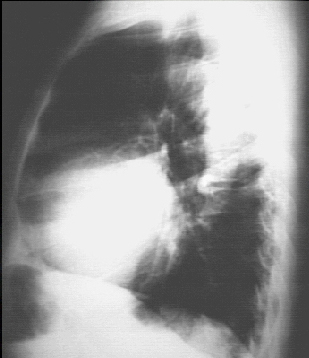

Lateral view

These chest X rays show left ventricular enlargement and a dilated aorta. The PA view demonstrates cardiomegaly, as evidenced by a cardiothoracic ratio greater than 50%. Note also the increased inferolateral cardiac border that is consistent with left ventricular enlargement due to volume overload. The ascending, transverse, and descending aortic shadows are also prominent. The lateral view shows left ventricular enlargement, as evidenced by posterior displacement of the left ventricular shadow.